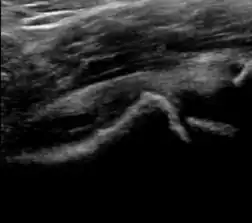

A step between the head and the physis can be detected in children with SCFE, while abnormalities in the femoral head contour may suggest the presence of LCPD. In both cases, radiographs are mandatory to confirm diagnosis and severity (Figure 12).[1]

Figure 12:

Normal ultrasound appearance of the femoral head-neck junction.

Joint effusion in transient synovitis of the hip.

Flattening of the femoral head in a patient with Perthes disease.

Step in the femoral head-neck junction in a patient with SCFE.